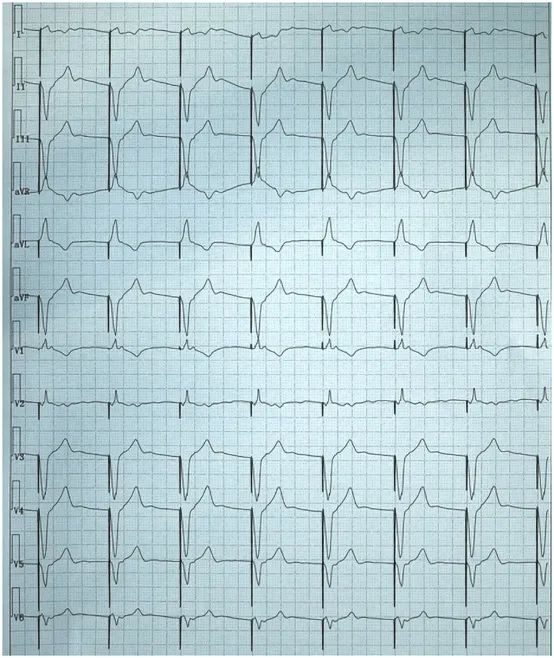

患者,女性,73岁,既往因病态窦房结综合征而植入右室单腔起搏器,此次门诊复诊行心电图检查如下。

图1. 患者门诊心电图呈VVI起搏(心率60次/分)。

大家可能注意到,患者此次复诊的心电图V1导联的QRS波向上,呈类“RBBB”样图形,和平常我们认为右室起搏时心电图呈类“左束支传导阻滞(LBBB)”的图形相反,难道是电极穿孔了?我们的“福尔摩斯医生”看到这份心电图,肯定地说没有穿孔,电极是在右室,而随后患者的胸片和胸部CT检查也证实了电极确实是在右室。

学习到这里,回到最开始的病例,该患者心电图的额面电轴位于左上象限,胸前移行导联≤V3。相信凭借大家的“火眼金睛”,此时也能一眼看出电极的位置是位于右室。这项技能你get了吗?